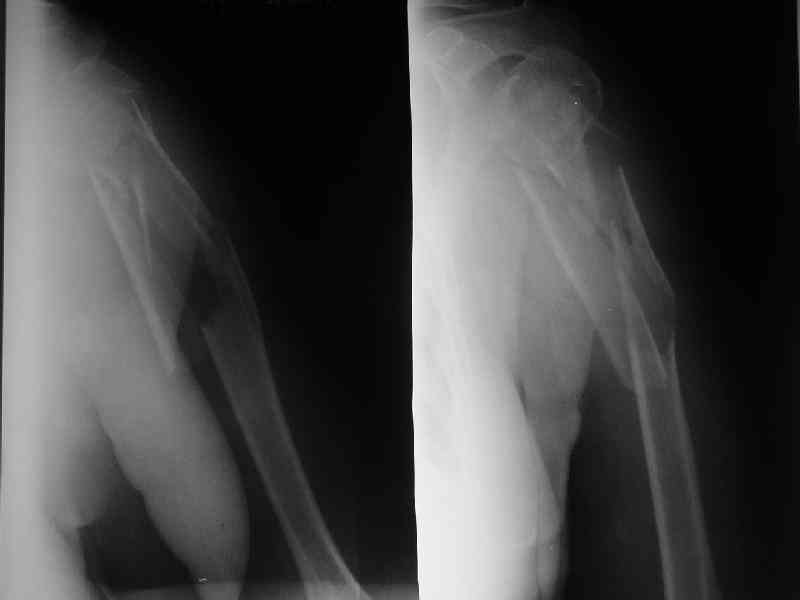

Здесь нет необходимости в серкляже. Вмешиваться на промежуточных отломках приходится, если есть угроза перфорации кожи, или промежуточный отломок попал в фасцию, как пуговица в петлю. В приложении сегментарный оскольчатый перелом плеча в проксимальном отделе, фиксированный больщеберцовым стержнем. Как видите, обошлось без серкляжа. Функция полная.

Александр, великолепные снимки! Вопрос - что за гвоздь?

Это укороченный большеберцовый стержень, которые делает предприятие "ЦИТО".

Доступные на тот момент гвозди для плеча имели худшие возможности фиксации в коротком проксимальном отломке.